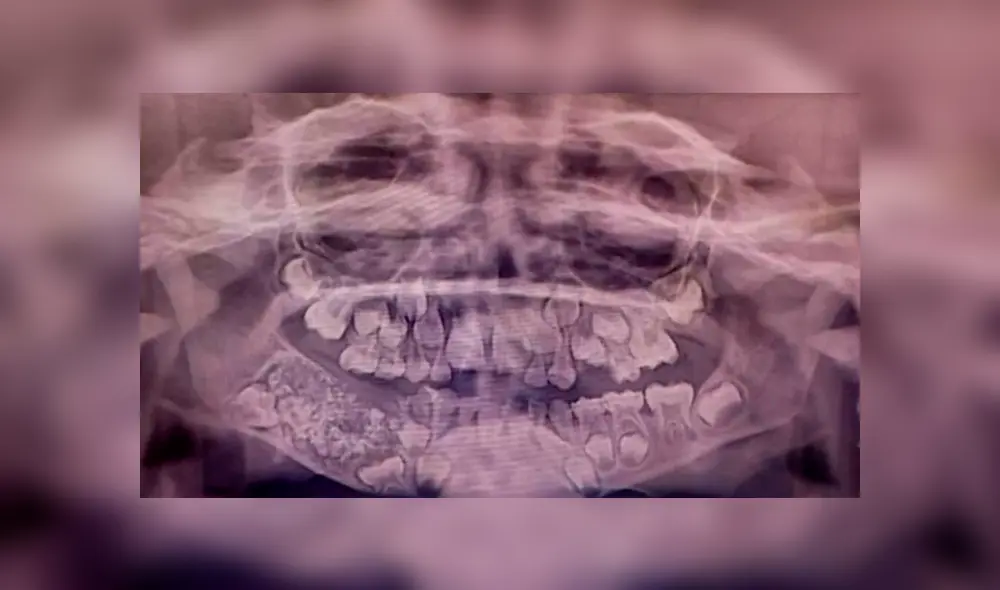

La radiografía y tomografía mostraron gran cantidad de dientes rudimentarios en un tejido similar a una bolsa.

Es la primera vez que hallan tantos dientes en una persona. Foto: Instituto de Ciencias Médicas y Técnicas Saveetha